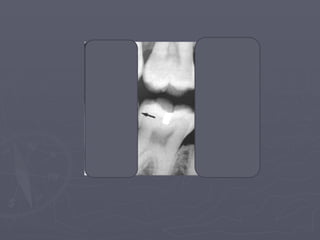

Mental Foramen

► It is the anterior limit of the inferior alveolar

canal.

► It doesn’t appear on every radiograph because

its opening is directed superiorly and posteriorly.

► It may be round, oblong, slit-like or very

irregular and partially or completely

corticated.

► The foramen is seen about half way between

the lower border of the mandible and the crest

of the alveolar process usually in the region of

the apex of the second premolar.

► Misinterpreted as a periapical pathosis.

mental

foramen

• 42.

Mental Foramen ► Itis the anterior limit of the inferior alveolar canal. ► It doesn’t appear on every radiograph because its opening is directed superiorly and posteriorly. ► It may be round, oblong, slit-like or very irregular and partially or completely corticated. ► The foramen is seen about half way between the lower border of the mandible and the crest of the alveolar process usually in the region of the apex of the second premolar. ► Misinterpreted as a periapical pathosis.